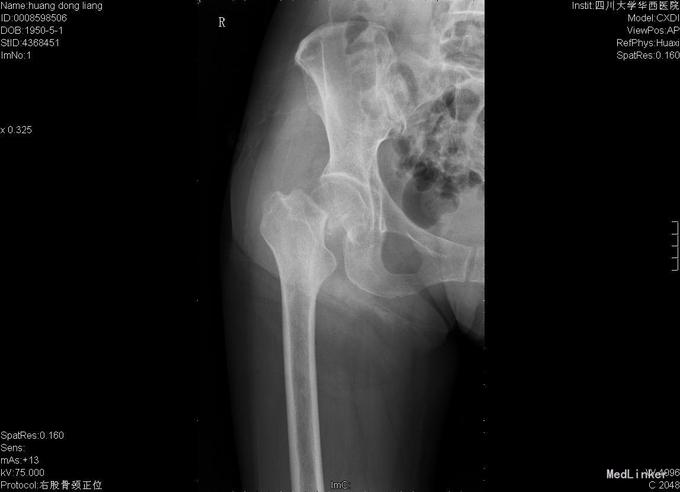

患者女,70岁,因"摔伤后右髋部疼痛、活动障碍10小时"入院,患者诉10小时前在家不慎滑倒,当即感觉右髋部疼痛、活动障碍,于当地医院急诊检查示:右股骨颈骨折,为求进一步诊疗故来我院。

查体:右髋部略水肿,右髋关节活动受限,不能负重。右髋部压痛(+),纵向叩击痛(+)。右髋关节活动受限,右膝及踝、足趾诸关节活动正常。 辅查:X线片示右股骨颈骨折,断端分离、错位。

入院诊断:右股骨颈骨折 诊疗计划:择期手术治疗,行右侧全髋关节置换。